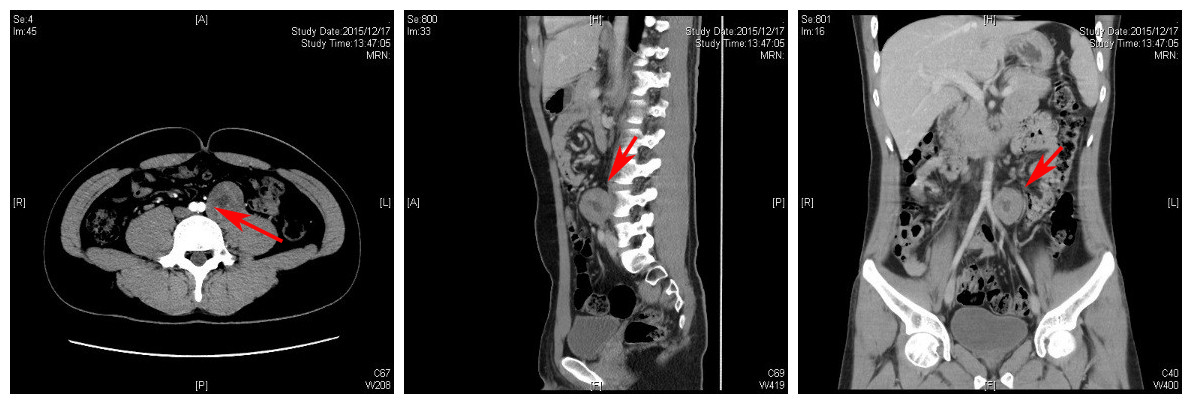

术前CT检查:“→”示为肿瘤位置

检查结果表明张先生的肿瘤占据腰椎椎旁及椎体前方,并将神经包裹在内,毗邻腹主动脉、输尿管等重要结构。王贵怀指出术中只有充分暴露肿瘤、保护好神经及大血管,才能达到安全切除肿瘤的效果。